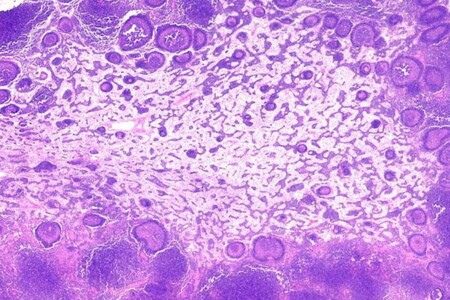

Burkittův lymfom je zhoubný nádor vycházející z lymfatické tkáně. Burkittův lymfom je nejčastěji lokalizován v oblasti dolní čelisti, méně často pak ve střevě, vaječníku, prsní žláze nebo ledvině. Nejčastější typ Burkittova lymfomu je tzv. endemický typ, vyskytující se téměř výhradně v Africe. Méně častý je pak tzv. evropský typ postihující kohokoliv bez rozdílu věku a pohlaví.